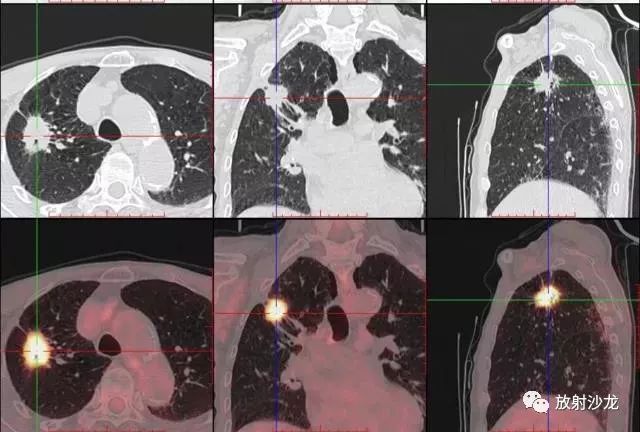

PET-CT是目前世界上最先進(jìn)的核醫(yī)學(xué)分子影像設(shè)備,中文稱為正電子發(fā)射計(jì)算機(jī)斷層/X 線計(jì)算機(jī)體層成像。

PET-CT等于PET+CT,包含PET(功能分子影像)與CT(解剖影像)的最優(yōu)化組合;即同時(shí)具有PET和CT的功能,但它絕不是二者功能的簡單疊加,因?yàn)镻ET與CT優(yōu)勢(shì)互補(bǔ),“1+1>2”。PET-CT除了具備PET和CT各自的功能外,其獨(dú)有的融合圖像,將PET圖像與CT圖像融合, 可以同時(shí)反映病灶的代謝,可以早期診斷疾病的同時(shí),明顯提高診斷的準(zhǔn)確性。